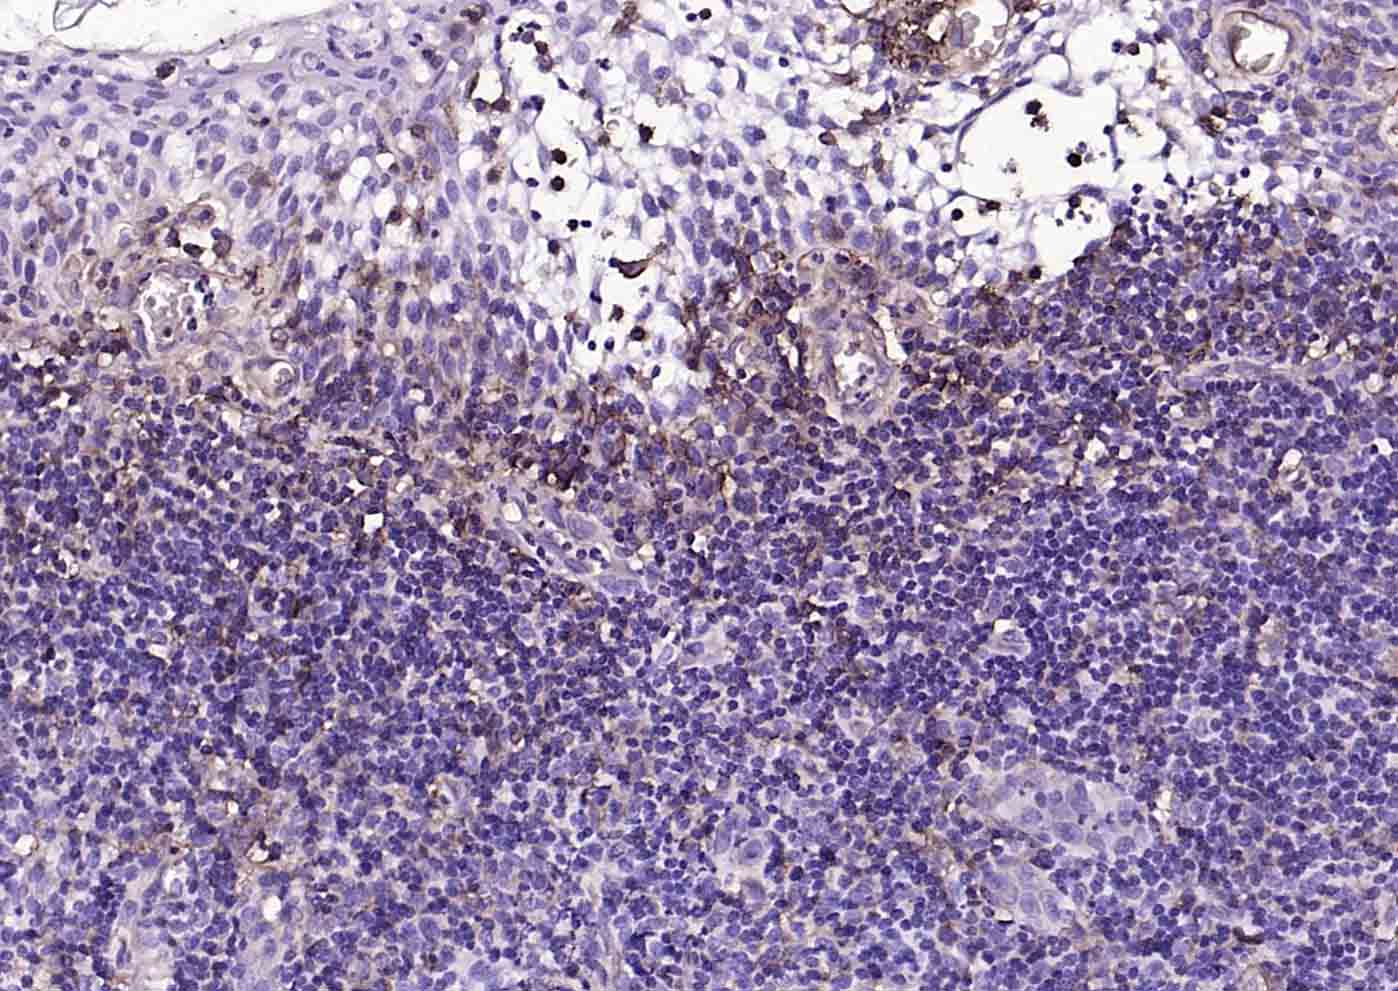

Paraformaldehyde-fixed, paraffin embedded (human tonsil); Antigen retrieval by boiling in sodium citrate buffer (pH6.0) for 15min; Block endogenous peroxidase by 3% hydrogen peroxide for 20 minutes; Blocking buffer (normal goat serum) at 37°C for 30min; Incubation with (CD39/ENTPD1) Monoclonal Antibody, Unconjugated (bsm-54043R) at 1:200 overnight at 4°C, followed by operating according to SP Kit(Rabbit) (sp-0023) instructionsand DAB staining.